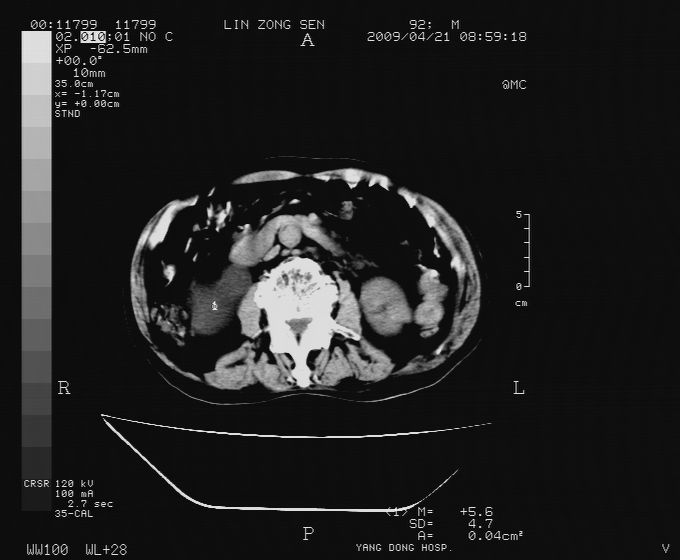

以下是引用卜一在2009-4-22 4:08:00的发言:[br]右肾积水伴输尿管上段积水!左侧肾多发囊肿!左侧腹壁软组织增厚,层次模糊,内密度较高—不排除血管瘤伴出血!